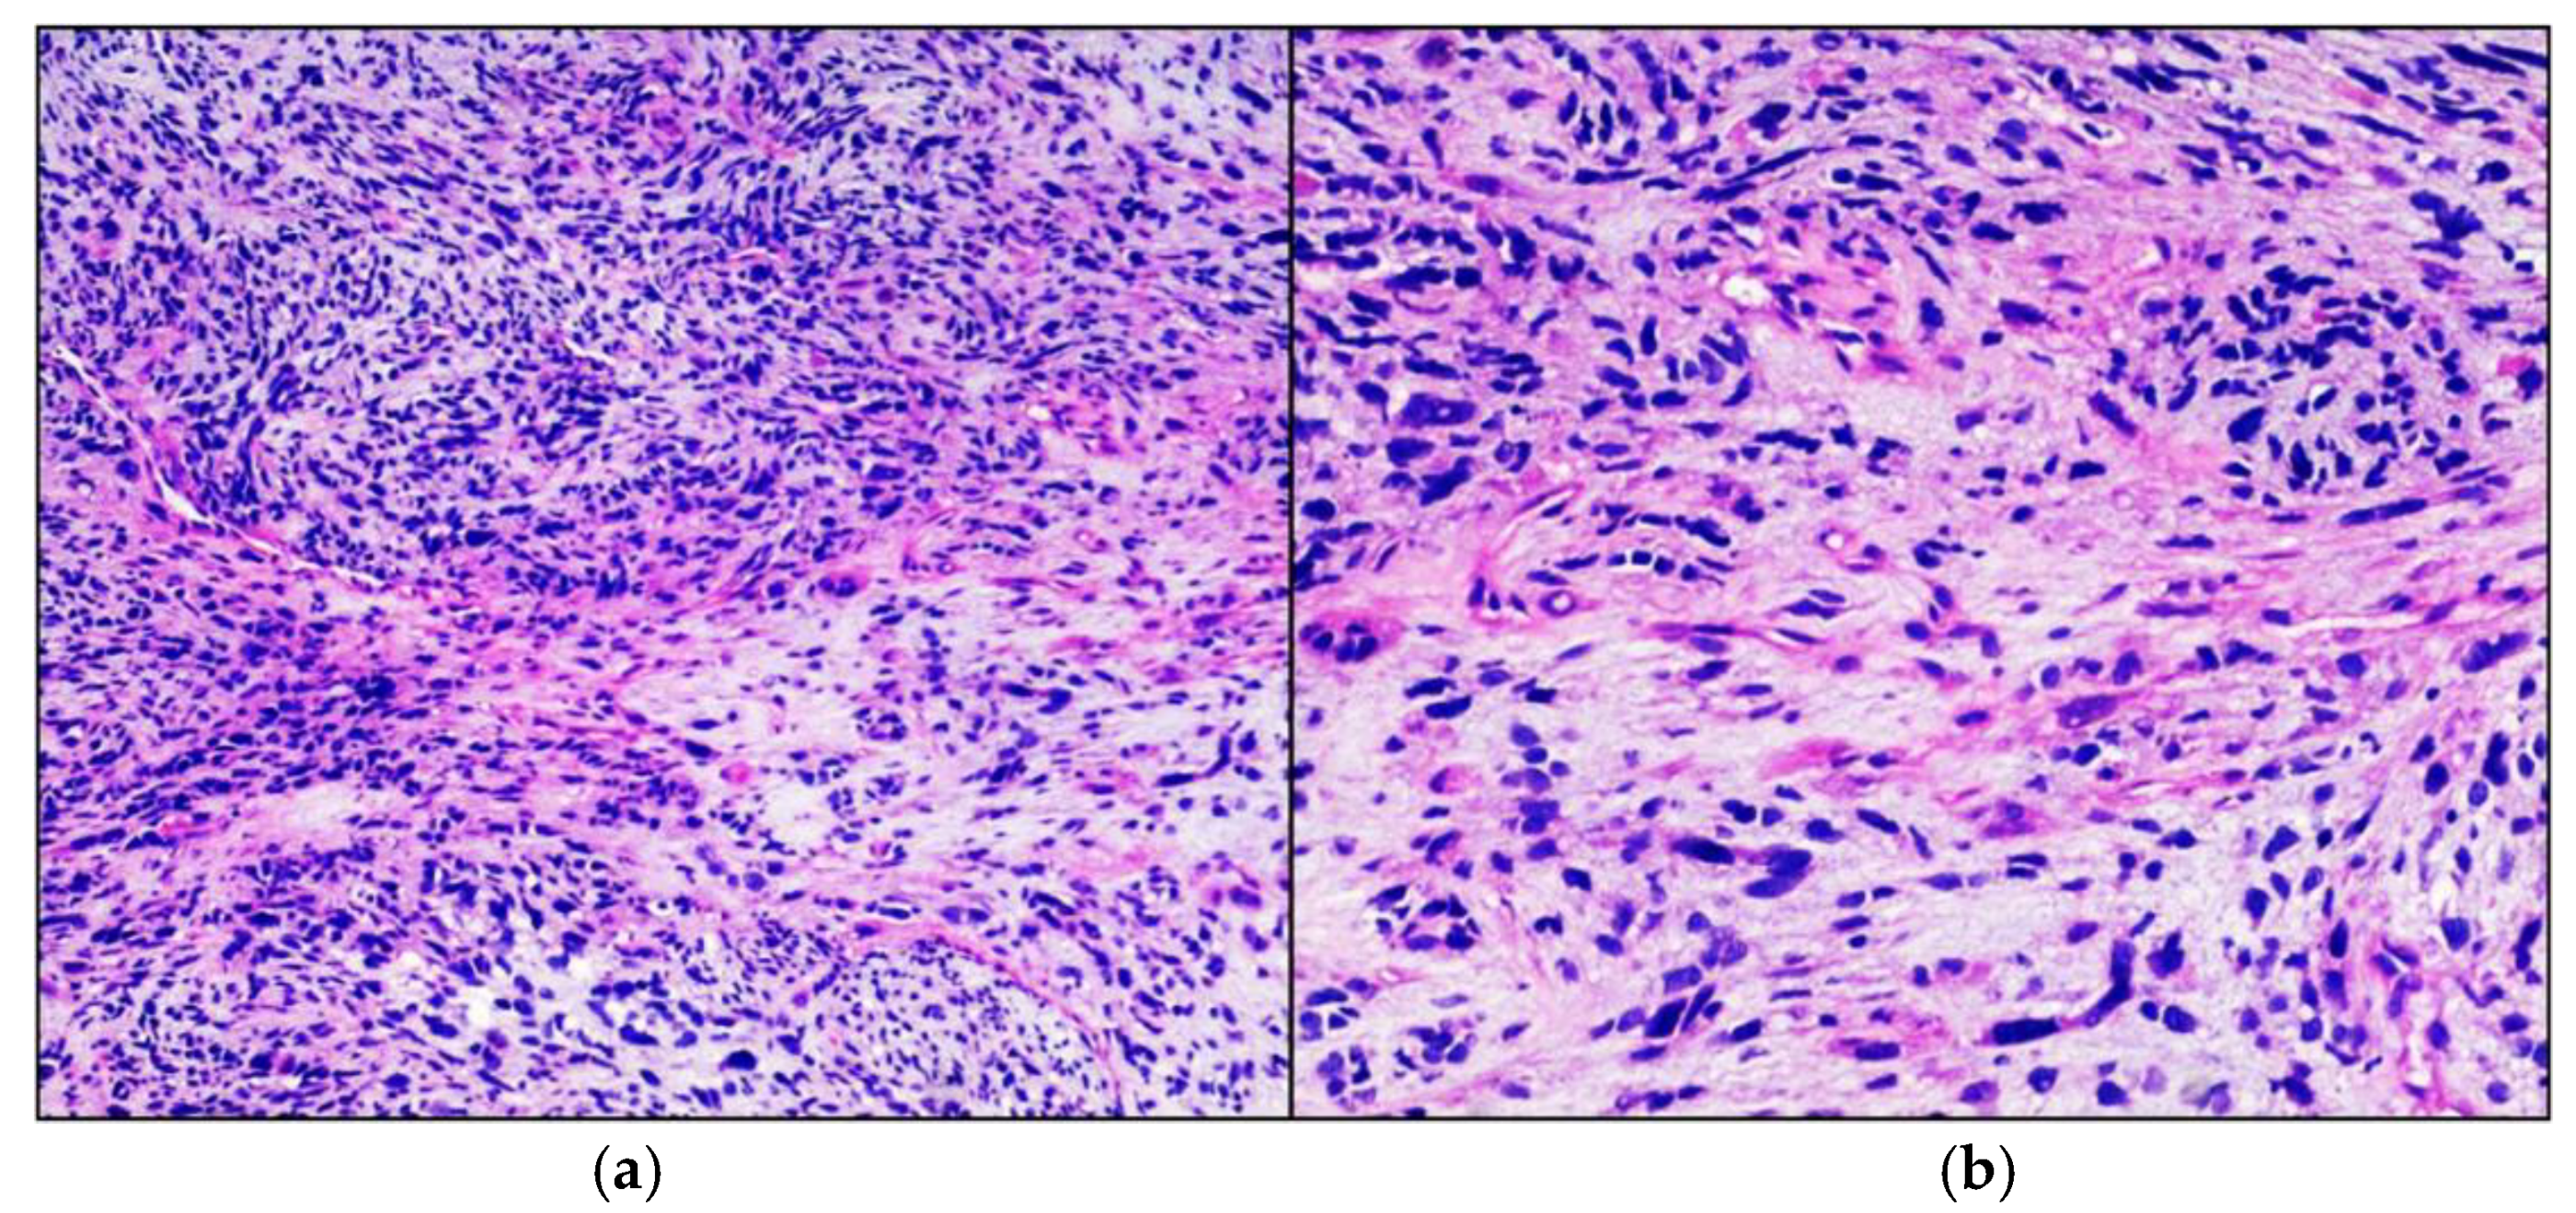

A previously healthy boy, born of full-term normal pregnancy, at the age of 18 months developed a swelling of the left thigh at the level of the femoral rectum muscle. Family medical history was relevant for ovarian cancer in the maternal great-grandmother and leukemia in his father’s cousin, 52 years old. He underwent an incisional biopsy of the lesion. The tissue was fixed in formalin, sampled and embedded in paraffin, sectioned at 4 µm and stained with haematoxylin-eosin. Histologically the neoplasm was characterized by a proliferation of fused cells and isolated large cellular elements, with large eosinophilic cytoplasm and voluminous and dysmorphic nuclei. The tumor cells showed consistent immunoreactivity for desmin and focally for smooth-muscle actin and actin HHF35, compatible with embrional rhabdomyosarcoma with fused and anaplastic cells (Figure 1). Molecular analysis was positive for MyoD1 and negative for PAX3-FOXO1, PAX7-FOXO1, PAX3-NCOA1, SRF4-NCOA1. A brain MRI performed at this stage did not show any anomaly.

Figure 1.

Embrional Rhabdomyosarcoma. Hematoxylin-eosin stained photomicrographs, with original magnification 100× (a) and 200× (b), showing characteristic intersecting fascicle of spindle cells with eosinophilic cytoplasm and iperchromic pleomorphic nuclei.